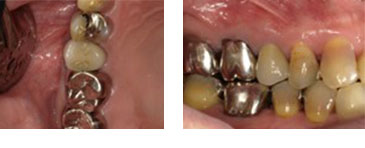

右下6番 フラップレス埋入(成熟側埋入)

BEFORE

AFTER

| 金額 | ¥420,000(税抜) |

| 期間 | 約2ヶ月半 |

| リスク | オペから6週までは過大な力がかかると骨の2次安定が得られないことがあるため、注意を要する。 |